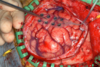

Graphical representation of Supratentorial vs. Infratentorial Tumors

Graphical representation of Supratentorial vs. Infratentorial Tumors

Major Supratentorial brain structure = Cerebrum

Major Infratentorial brain structures = Cerebellum & Brainstem